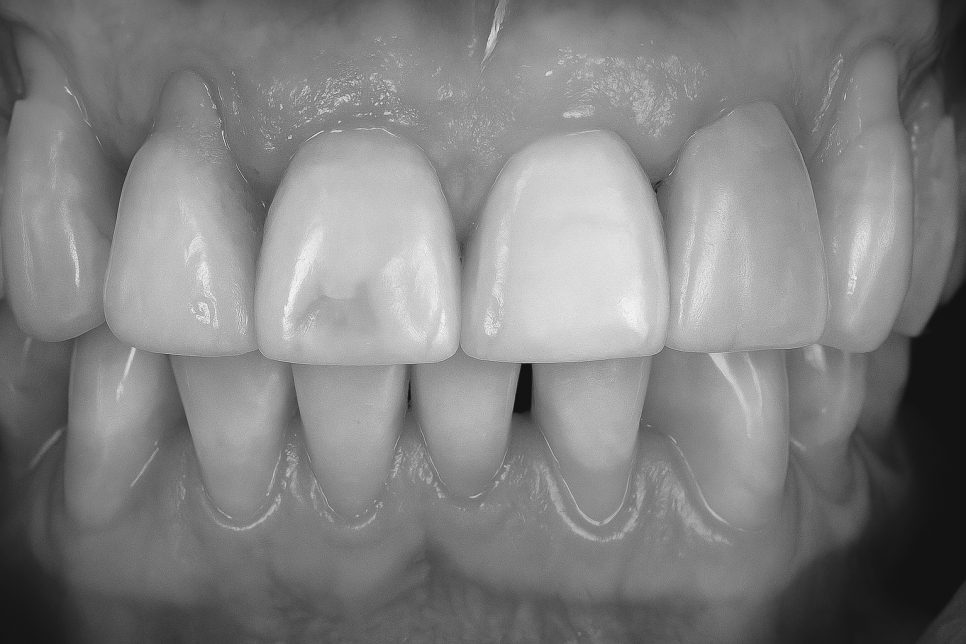

그리고 이렇게 패여버린 홈은 미관을 해칠 수 있어

미용 문제와 자신감 저하를 가져올 수 있고,

여러 합병증으로도 이어질 수 있답니다.

먼저는 레진 복원

방법을 설명 드리겠습니다.

마모 단계가 경미할 때는 복합레진을 통해

패인 부위를 충전시켜줄 수 있으며,

이때 본래 자연치와 유사한 재료를 쓰기 때문에

미관에도 큰 도움이 될 수 있답니다.